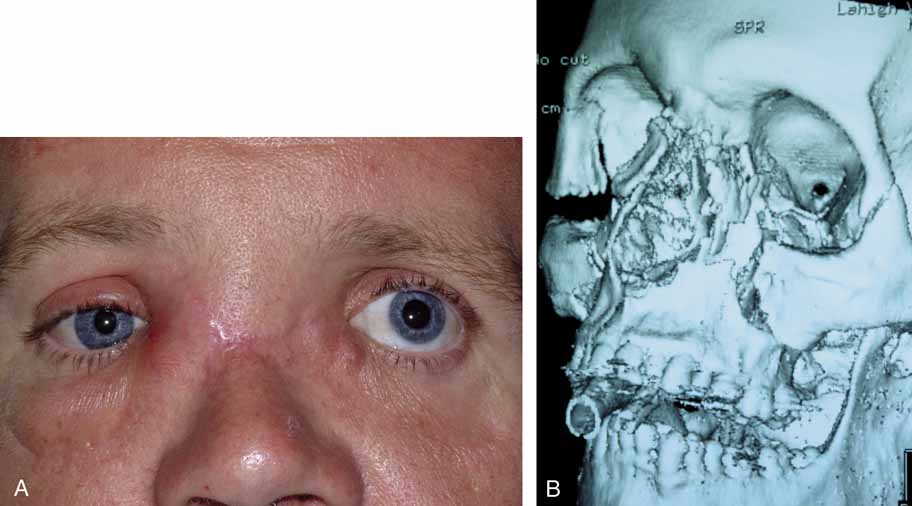

ABNORMALITIES OF THE PUNCTA AND CANALICULI (UPPER SYSTEM BLOCKS) Surgery of the punctum should be as conservative as possible. For simple

congenital veils, gentle puncture followed by dilation and irrigation

often will suffice. For greater degrees of atresia, however, injection

of methylene blue into the lacrimal sac through the skin may be of

value, particularly when the surgeon suspects that the canaliculus may

be involved (Figs. 50 and 51). The surgeon can apply pressure over the lacrimal sac area and look

for retrograde flow of dye through the lid margin. If the dye is not

visible, an incision in the lid margin can be made in the area of the

lacrimal papilla, if present. If the punctum is not present, an incision

can be made approximately 8 mm lateral to the medial canthal angle (Fig. 52). If dye is visible, the channel is normal (Fig. 53). If suction of the nose reveals dye, the sac and duct are clearly

patent, and a stent of Silastic tubing can be placed throughout the

nasolacrimal system, as is done for dacryostenosis (Fig. 54). However, if there is obstruction in the lower system, a DCR will

be necessary. Silastic tubing can be run through the entire upper and

lower canaliculus and through a DCR opening.  Fig. 50 Both puncta are absent in the left eye. Fig. 50 Both puncta are absent in the left eye.